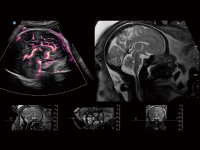

丰富的血流动力学检测技术,可在不同医疗场景中高效捕捉血流信号,助力临床诊疗。

在传统血流的基础上优化扫查和算法策略,能够更好的抑制组织信息,提炼红细胞运动信息,得到更高帧频,高灵敏度和分辨率的血流信号,还原更真实的血流动力学。

通过光照模型,使二维血流显示出立体的效果,增加血流的敏感性、成束性,减少外溢。可以和其他不同的血流技术联合使用,融合不同技术的优势。轻松应对微小血管,增强血流的立体效果,提升视觉敏感性。